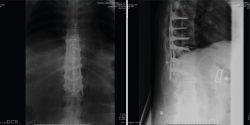

En la Figura 1 se muestra la primera radiografía que le realizan en el centro hospitalario más cercano al accidente. En ella visualizamos un perfil dorsolumbar realizado sobre la camilla de transporte con 2 imágenes. Por un lado, una apertura anterior patológica a través de disco a nivel dorsal, concretamente T10/T11. También observamos una sindesmofitosis de todo el raquis que conocemos como “caña de bambú”. Esto orienta a una enfermedad reumática, concretamente una espondiloartitis anquilosante(1).

Figura 1. Radiografía inicial.